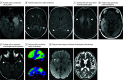

Results: A total of 107 patients were misdiagnosed with autoimmune encephalitis, and 77 (72%) did not fulfill diagnostic criteria for autoimmune encephalitis. The median (IQR) age was 48 (35.5-60.5) years and 65 (61%) were female. Correct diagnoses included functional neurologic disorder (27 [25%]), neurodegenerative disease (22 [20.5%]), primary psychiatric disease (19 [18%]), cognitive deficits from comorbidities (11 [10%]), cerebral neoplasm (10 [9.5%]), and other (18 [17%]). Onset was acute/subacute in 56 (52%) or insidious (>3 months) in 51 (48%). Magnetic resonance imaging of the brain was suggestive of encephalitis in 19 of 104 patients (18%) and cerebrospinal fluid (CSF) pleocytosis occurred in 16 of 84 patients (19%). Thyroid peroxidase antibodies were elevated in 24 of 62 patients (39%). Positive neural autoantibodies were more frequent in serum than CSF (48 of 105 [46%] vs 7 of 91 [8%]) and included 1 or more of GAD65 (n = 14), voltage-gated potassium channel complex (LGI1 and CASPR2 negative) (n = 10), N-methyl-d-aspartate receptor by cell-based assay only (n = 10; 6 negative in CSF), and other (n = 18). Adverse reactions from immunotherapies occurred in 17 of 84 patients (20%). Potential contributors to misdiagnosis included overinterpretation of positive serum antibodies (53 [50%]), misinterpretation of functional/psychiatric, or nonspecific cognitive dysfunction as encephalopathy (41 [38%]).

Figures